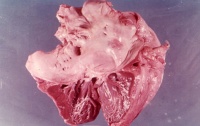

病理变化先瓣膜交界处和基底部炎症水肿赘生物形成,

由于纤维化和(或)钙质沉着,瓣叶广泛增厚,粘连,腱索融合,缩短,瓣叶僵硬,导致瓣口变形和狭窄,狭窄显著时成为一个裂隙样的孔。按病变程度分为隔膜型和漏斗型。隔膜型主瓣体无病变或病变较轻,活动尚可;漏斗型瓣叶明显增厚和纤维化,腱索和乳头肌明显粘连和缩短,整个瓣膜变硬呈漏斗状,活动明显受限。常伴有不同程度的关闭不全。瓣叶钙化进一步加重狭窄,并可引起血栓形成和栓塞。先天性的二尖瓣狭窄,其瓣叶增厚、交界融合、腱索增厚或缩短、乳头肌肥厚或纤维化,瓣上可有狭窄环、瓣下可有纤维带。最具特征性是只有一个乳头肌的二尖瓣降落伞状畸形,两个瓣叶的腱索都连接在此乳头肌上,整个瓣膜开加降落伞。